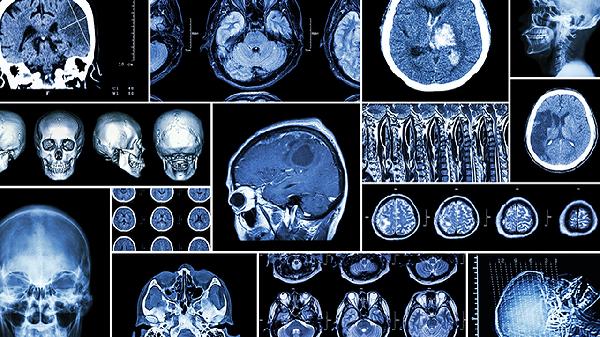

超声检查是诊断胎儿胸腔积液的主要手段,通过动态观察积液量变化评估胎儿预后。超声可测量积液深度、判断是否合并其他结构异常,如纵隔移位或胎儿水肿。对于轻度积液且无进展的病例,通常建议每两周复查一次超声。